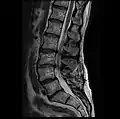

- MRI lumbar spine with degeneration, post-hemilaminectomy L4-5 (sagittal T2 FRFSE)